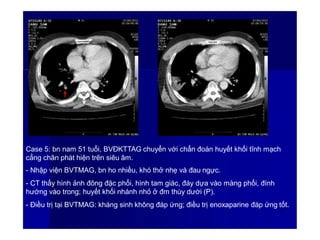

Case 5: bn nam 51 tuổi, BVĐKTTAG chuyển với chẩn đoán huyết khối tĩnh mạch

cẳng chân phát hiện trên siêu âm.

- Nhập viện BVTMAG, bn ho nhiều, khó thở nhẹ và đau ngực.

- CT thấy hình ảnh đông đặc phổi, hình tam giác, đáy dựa vào màng phổi, đính

hướng vào trong; huyết khối nhánh nhỏ ở đm thùy dưới (P).

- Điều trị tại BVTMAG: kháng sinh không đáp ứng; điều trị enoxaparine đáp ứng tốt.